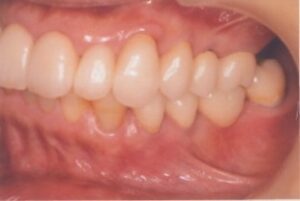

- 10年前から他の歯科医院にて部分的な治療を受けたが、見た目が良くない・噛めないとのことで再治療を希望された。アングルクラスⅠであった。左上奥歯がない。

- 上顎左側にインプラントを3本し、

- オールセラミック4本にて被せ物を行なった。

- 審美的な仕上がりで、患者自身も満足した。23年経過し良好である。

現在は2〜3ヶ月おきのメインテナンス中である。